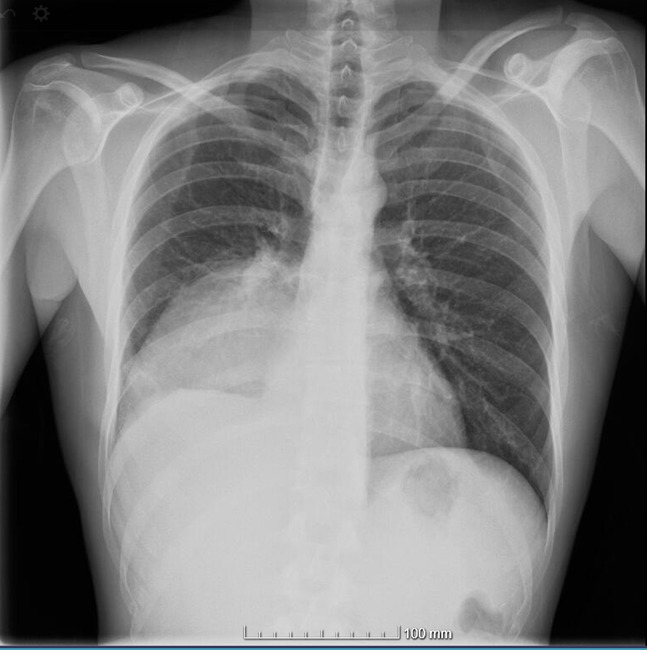

Se realiza una radiografía de tórax informada como atelectasia basal derecha. El paciente es ingresado en planta de Neumología. Realizan un TAC de tórax con contraste, que confirma un derrame pleural compatible con empiema como primera posibilidad. El paciente evolucionó favorablemente tras antibioterapia y drenaje de 750 cc de material purulento, con mejoría clínica y radiológica. Fue dado de alta a domicilio con el diagnóstico de empiema pleural derecho, probablemente secundario a diseminación hematógena por boca séptica.